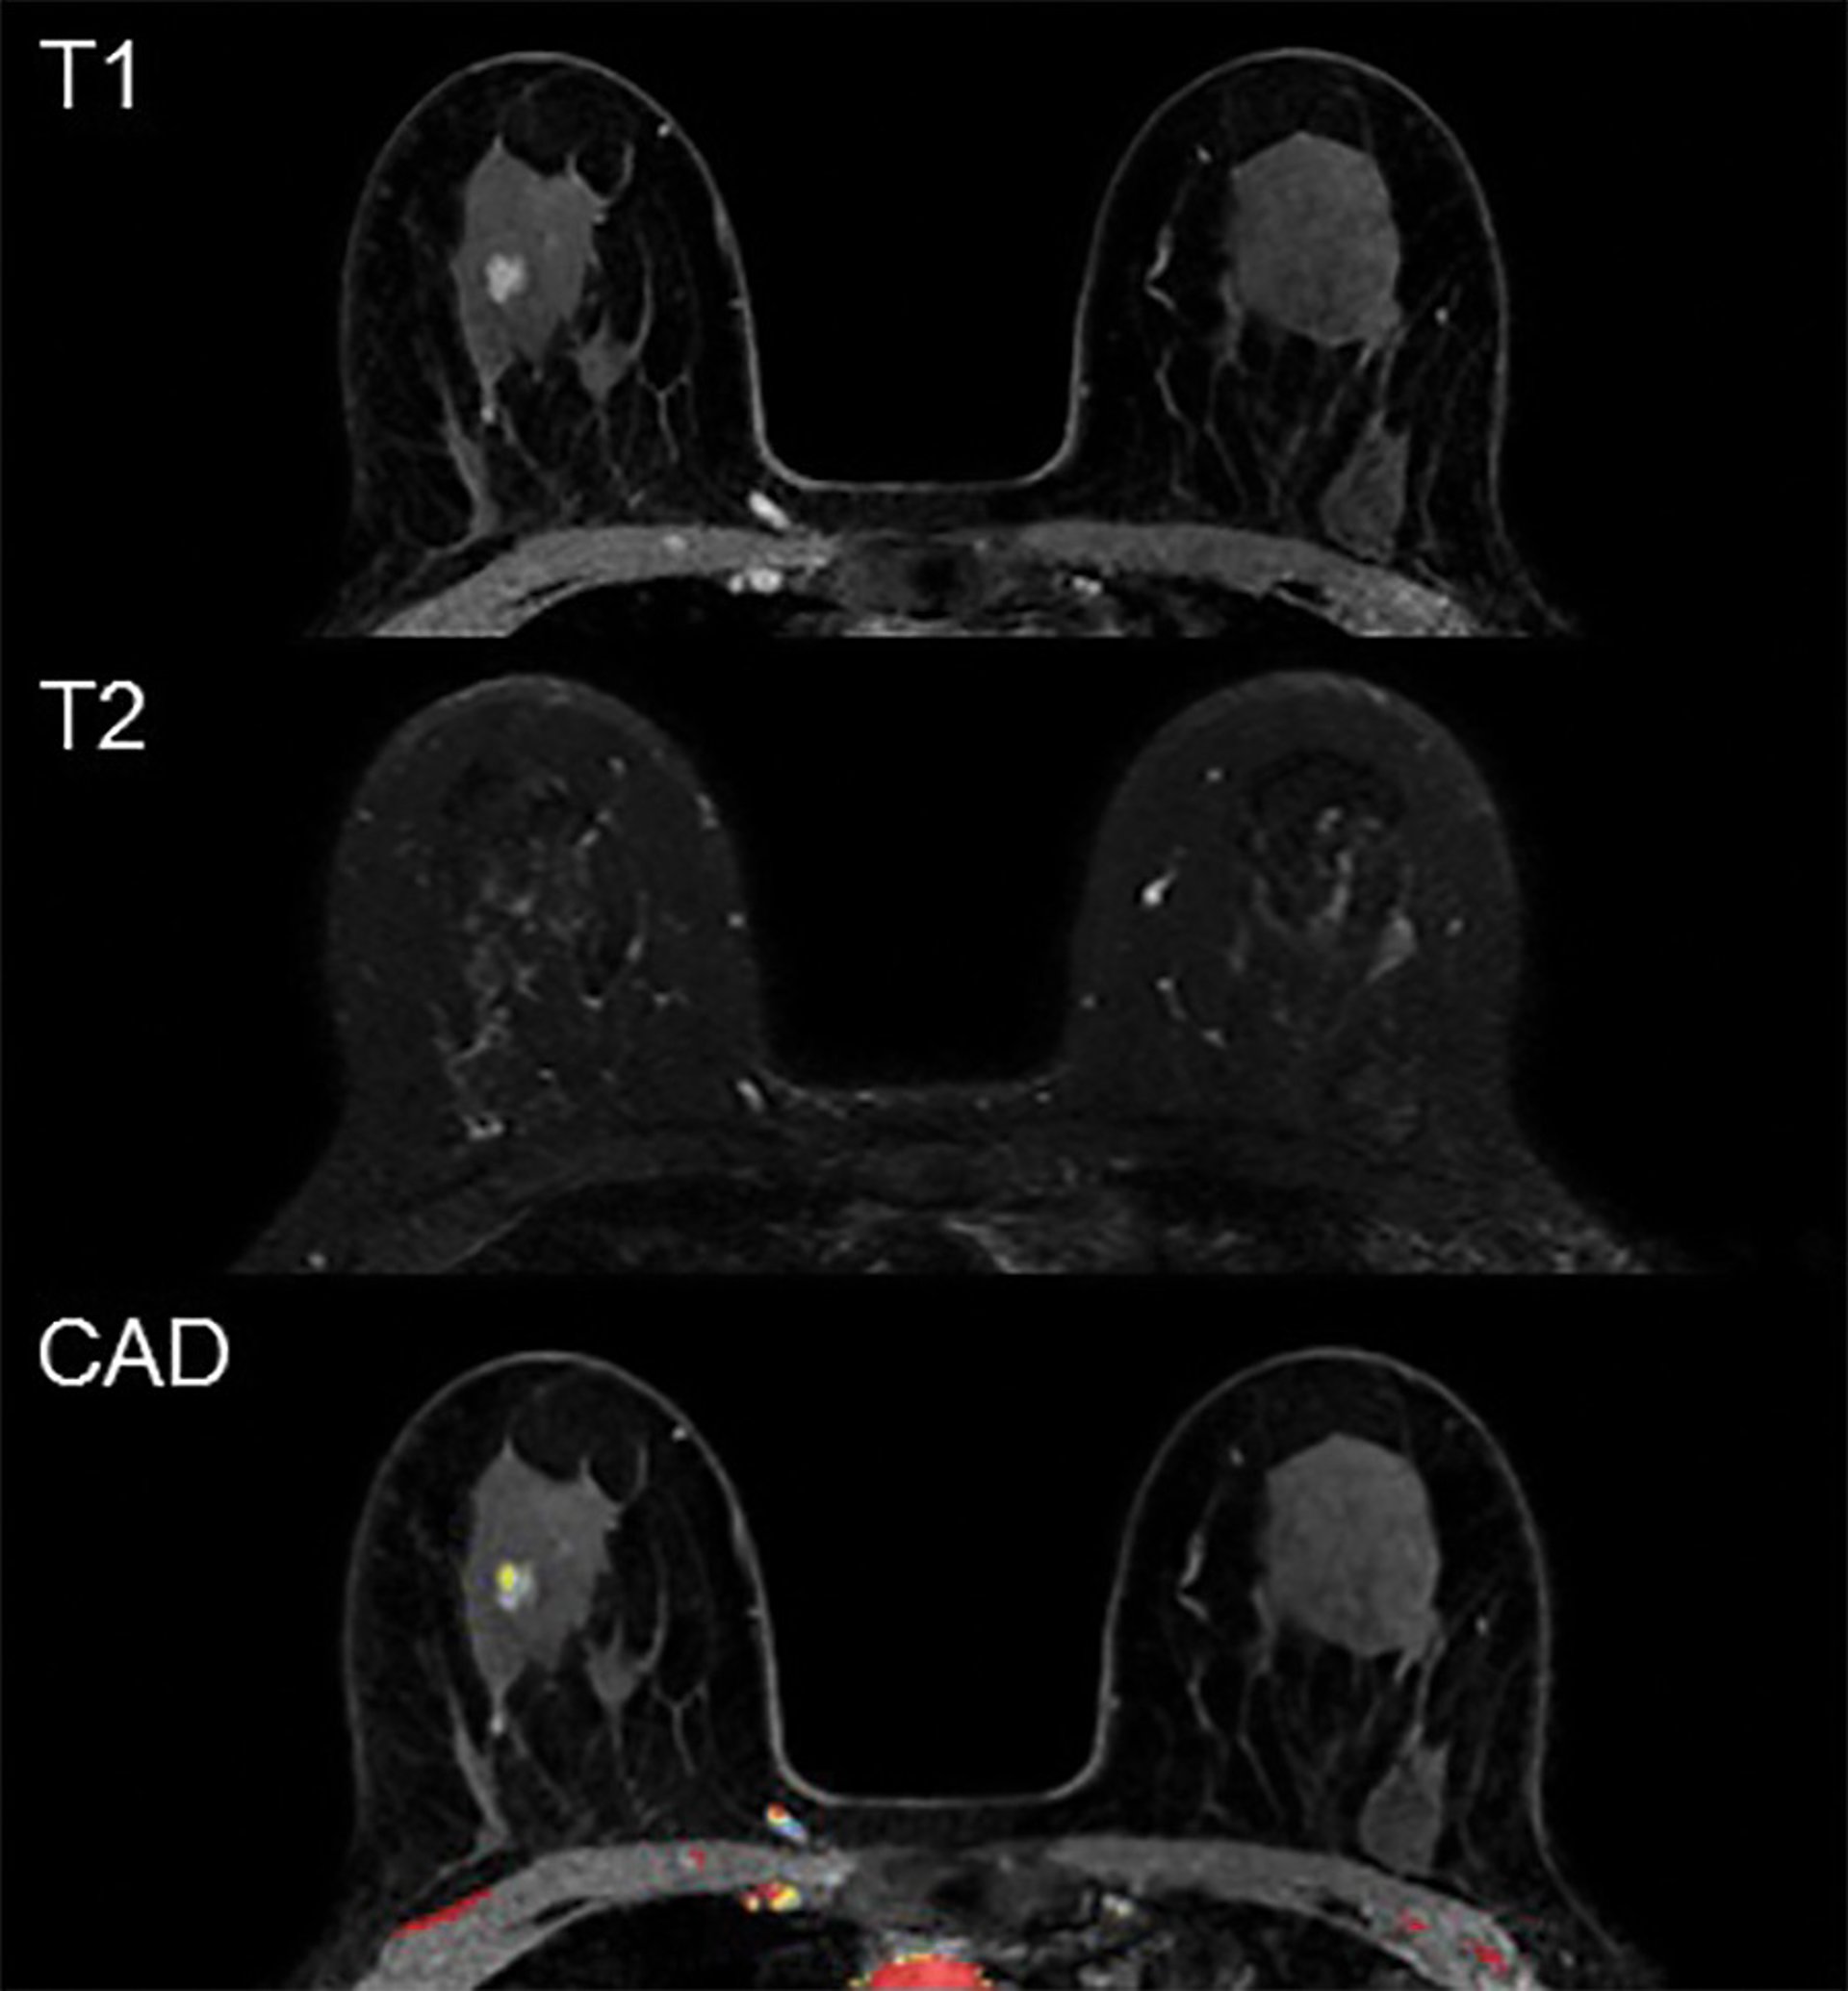

Ejemplo de resonancia magnética falsa positiva.

Ejemplo de resonancia magnética falsa positiva. - RADIOLOGICAL SOCIETY OF NORTH AMERICA